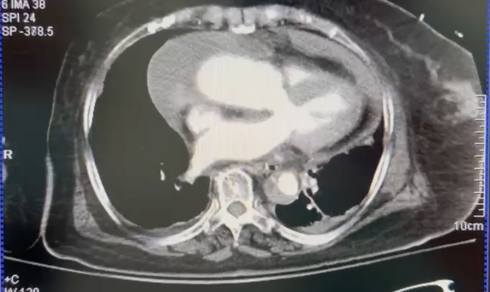

术后患者拔出气管导管后,开始出现心率增快,伴血压低,麻醉科医师予以升压、补液等处理,效果不佳,麻醉医师完善床旁心超如下图:

当天的值班医师小L首先为患者行重症超声检查,以期判断休克类型。由于声窗及患者体型等限制,无法获取标准能够进行定量测量切面,结合前期术后超声,该患者心脏超声表现为:

剑突下切面见右房室壁周包绕低回声影

因此,通过查体及重症超声初步评估,值班医师小L考虑患者梗阻性休克可能性最大,而梗阻的部位首先考虑为心包积液/血所致的心包填塞。

明确休克类型及诊疗方向后,接下来,值班医师小L为患者建立的中心静脉,测得CVP 20mmHg,因此更进一步证实了心包填塞的可能。此时,顺着这一线索,结合患者术后心脏超声的主动脉内的内膜片、不对称的双下肢花斑,进一步考虑病因可能为主动脉夹层撕裂所致的心包积血等,因此,为外出行CTA检查,同时为患者进行了镇痛镇静、气管插管。

主动脉夹层及壁间血肿

心包积液/血

临床考虑诊断的心包填塞